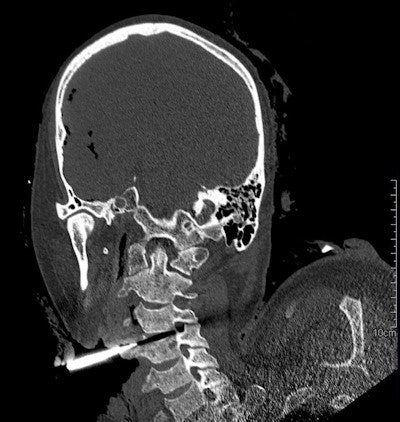

CT angiography (CTA) and other methods can shed light on death investigations in ways that autopsy can't. CTA, for example, allows doctors to look for bleeding points, while dual-beam CT depicts soft-tissue differentiation and bruising, and the technique is useful to investigate postsurgical deaths and identify trauma areas deep in the pelvis and around the spine, which are usually difficult to see without extensive dissection.

For Ranson, CT provides a 3D record that can be consulted long after the body has been buried or cremated, when improved software might provide better detection and visualization of disease, foreign objects, and trauma, or when a second opinion is desired. Other benefits include early detection of dangerous elements, including sharp objects such as mesh or stents, and of infectious diseases indicated by cavitating lesions found in tuberculosis, for example.

Awareness of the pitfalls related to forensic questions is also vital. Postmortem CT can, for example, identify the cause of death in a case of hypertensive intracerebral hemorrhage, but imaging cannot clarify the manner of death in such cases; hypertension may be a natural event or due to cocaine intoxication, and toxicological analysis is required to determine this.